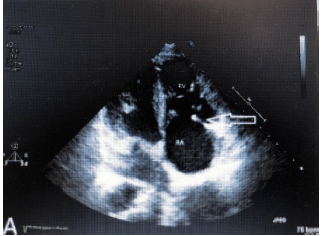

Paciente de 40 anos do sexo feminino, deu entrada na emergência referindo quadro de diarreia volumosa, confusão mental e flushing cutâneo. Relata ainda, perda de peso e intensificação dos sintomas que já duram mais de 3 meses. Ao exame físico, chamava atenção um sopro em foco tricúspide e sibilos pulmonares. Foi estabilizada e encaminhada ao laboratório de ecocardiografia que adquiriu a seguinte imagem ao exame transtorácico, compatível com achados ecocardiográficos da síndrome carcinoide.

Sobre a síndrome carcinoide, analise as afirmativas abaixo.

I. O diagnóstico de Síndrome carcinoide tem como base achados clínicos típicos e é confirmado pela dosagem de ácido 5-hidroxindolacético (5-HIAA), um produto final do metabolismo da serotonina, em urina coletada em 24 horas

II. O ecocardiograma nessa patologia geralmente mostra acometimento mitral concomitante em 20% dos casos

III. A fibrilação atrial está presente em menos de 20% dos casos e foram registradas apresentações graves com relatos de morte súbita

IV. Patologia frequentemente associada a tumores secretores de Dopamina.

Estão corretas as afirmativas: